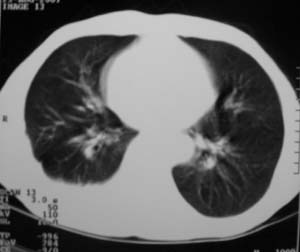

男,54岁,无任何不是感.体检发现右肺部阴影.现行ct进一步确诊.

右侧胸廓塌陷,肋间隙变窄,肋骨增生变粗,脏壁层胸膜肥厚、钙化。符合陈旧性结核性脓胸改变

右侧包裹性积液伴胸膜钙化.

右侧包裹性积液并胸膜钙化,性质还是结合穿刺细胞学检查的好,结核性、化脓性均会有钙化。

右侧胸膜肥厚、粘连、钙化。

周围都钙化了应该不是积液了吧,这样都没有不适感,病史不详